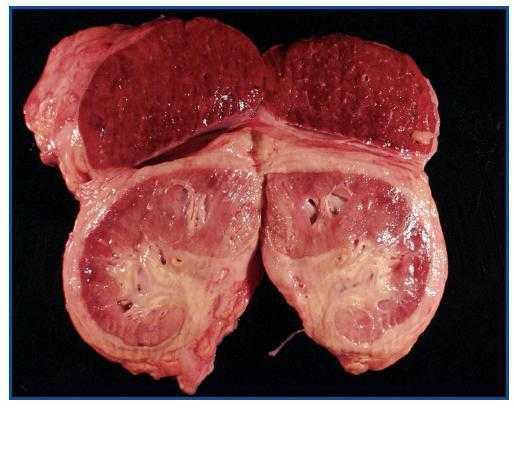

La necropsia demostró un proceso fibrosante sistémico (Figuras 1-4), con afectación de pelvis menor, retroperitoneo, en coraza alrededor de riñones, glándulas suprarrenales y páncreas, abarcando espacio periesplénico y perihepático; y mediastínico, en coraza alrededor de pericardio, arco aórtico y grandes vasos; y paquipleuritis derecha con fibrosis calcificada. Se apreciaron también: pancreatitis crónica fibrosa asociada, atrofia testicular, fenómenos de enfermedad aterombólica, hipertrofia ventricular izdª, y hepatopatía fibrosa crónica, en el contexto de un paciente con arteriosclerosis generalizada severa, con repercusión renal -nefroangiosclerosis bilateral con atrofia renal derecha, encefálica –infarto antiguo quístico izquierdo a nivel de ínsula-, y de colon –colitis isquémica rectosigmoide.

Figura 3.